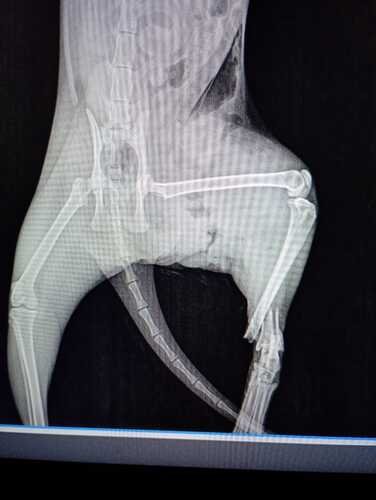

Mia, nossa gatinha, sofreu uma fratura exposta na patinha traseira devido a um ataque de cachorros no dia 17/12 e necessita de uma amputação urgente.